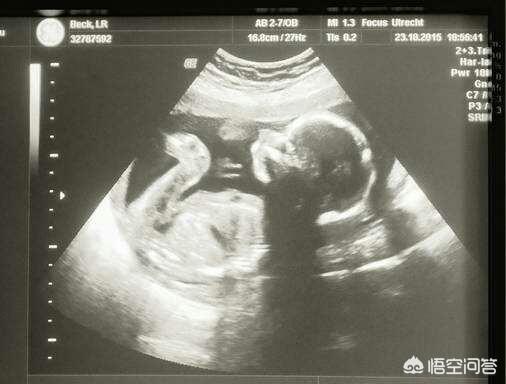

1.妊娠中の胎児異常の検出には、NT検査、ダウン症スクリーニング、4D超音波スクリーニング、DNA検査、羊水穿刺がある。

私たちの超音波検査ですべての問題を発見する方法はありません。多くの親は、陣痛や分娩の検査で定期的な検診を受けているのに、なぜ心房や心室の欠陥があるのだと言うでしょう。実際、このような単純な心臓病や、眼球が小さいなどの問題をすべて発見する方法はない。複雑な先天性心疾患や、脳の発達異常や無脳症などの奇形の多くは、超音波検査で発見することができ、奇形児の出産を避けるために適時分娩を誘発することができる。

定期的な陣痛検査で多くの問題が明らかになることもある。例えば、胎児が明らかに小さいことがわかれば、栄養補給のために輸液が必要になるかもしれないし、胎児が非常に大きければ、帝王切開で出産しなければならないかもしれない。また、子癇前症と呼ばれる危険な病気もあり、検診で早期に発見されることもあるが、対処が間に合わなければ、胎児と母体を危険にさらすことになりかねない。妊婦検診には限界があるとはいえ、母子の安全を守るためには、少なからず必要なことなのである。

妊娠中、超音波検査は、多くの妊娠中の母親のために、そのような疑いを持っている、つまり、妊娠の検査では、より多次元3次元、4次元超音波の検査に関与することになります。自分自身と胎児にさらなる懸念がある場合は、ダウン症のスクリーニング、羊水穿刺や他のより繊細で詳細な検査が使用されます。